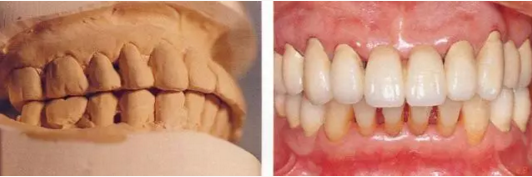

0.png

▲圖16-11,12

▲圖16-11 正畸治療結(jié)束后的研究模型。覆蓋有所改善。

▲圖16-12 佩戴最終修復(fù)體后的狀態(tài)。